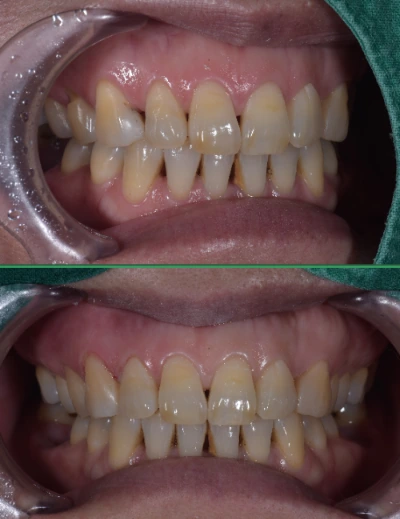

왼쪽 앞니의 레진치료 왼쪽 송곳니 부위의 부적절한 레진을 제거하고 좀 더 자연스럽게 수복..

오른쪽 송곳니의 레진치료 마찬가지로 부적절한 친구들 떼버리고 예쁘게 수복.

오늘도 꽤 괜찮은 레진을 해버리며 안타를 하나 쳤다는 기쁨이 밀려옵니다.